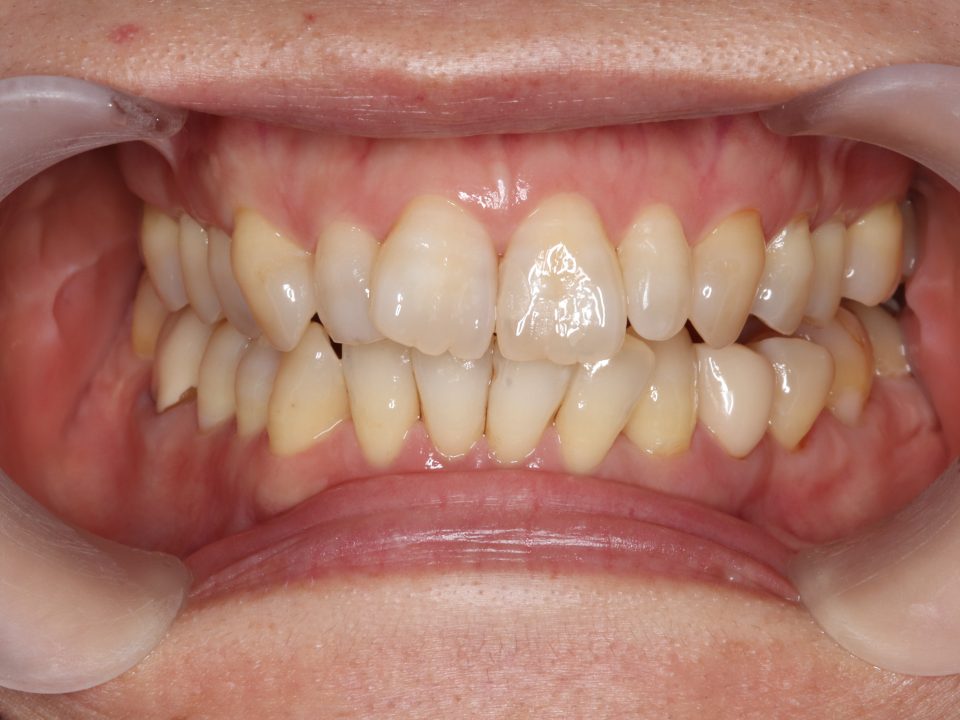

矯正治療前

40代女性の患者さんです。

上の前歯が曲がっていることが気になり矯正治療を始めました。